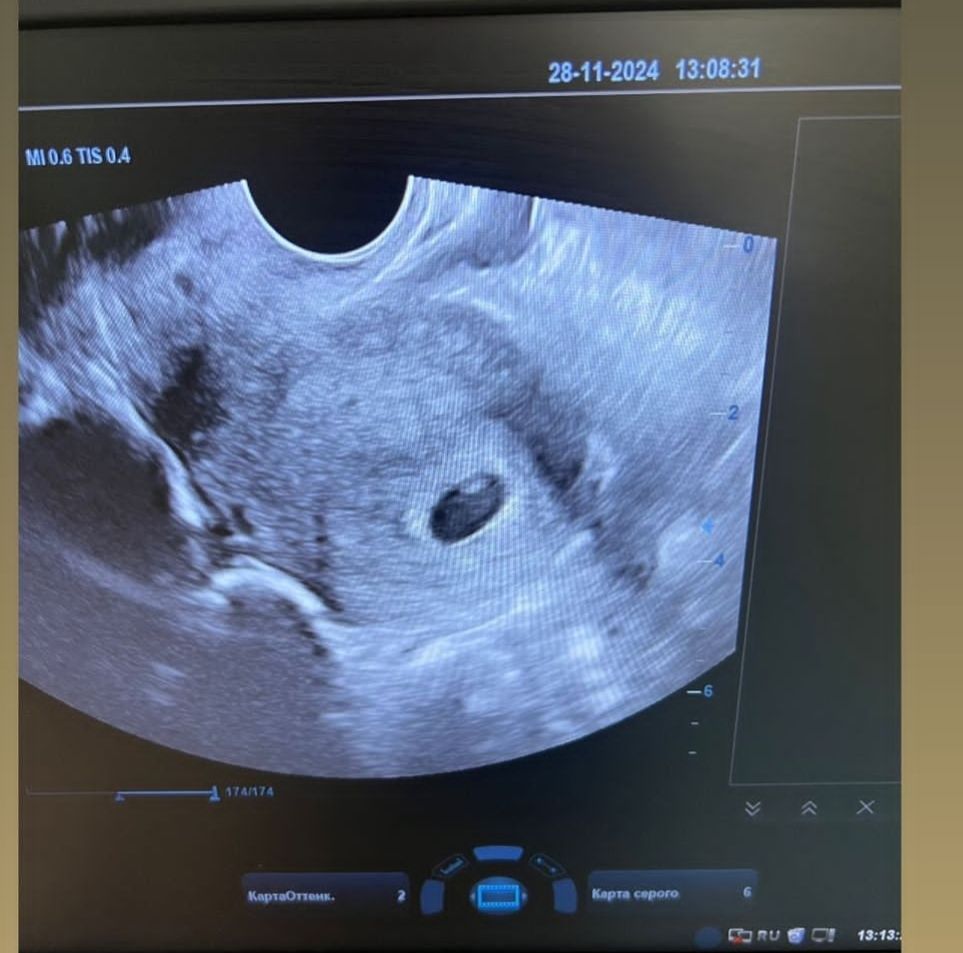

Первое узи

УЗИ 7 недель или 33 дпп Многокамерная , мелкосетчатая киста